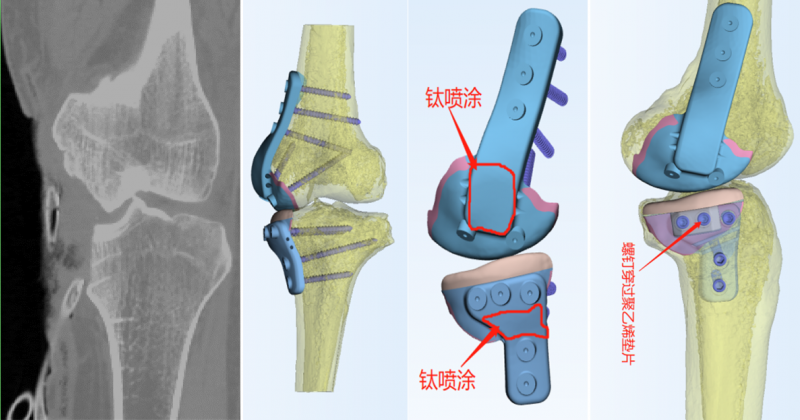

下一步如何处理,怎样重建关节的稳定性?非常棘手。为此,烟台山医院急诊创伤中心李宏彦主任及时组织了全院病例讨论,常黎明副院长、骨科孙涛主任提出了利用3D打印技术为张先生打印假体的设想,以此精准修复骨关节缺损,恢复膝关节的完整性和功能性。结合损伤情况,手术可分两阶段进行:首先进行清创,待创面无感染后联合显微外科完成带蒂皮瓣覆盖创面的相关治疗;接下来借助3D打印技术制作假体,此后再进行假体植入及内侧副韧带重建。

3D打印植入假体的设计过程。

结合影像学资料及症状体征,烟台山医院为张先生打印了一个与其膝关节缺损部分形态匹配、生物力学适配的假体。在当天的手术中,烟台山医院骨科孙涛主任与急诊创伤中心李宏彦主任为张先生植入了3D打印的假体,并完成了内侧LARS韧带重建术,术中测试,关节活动良好、稳定性良好。目前张先生正在康复中。